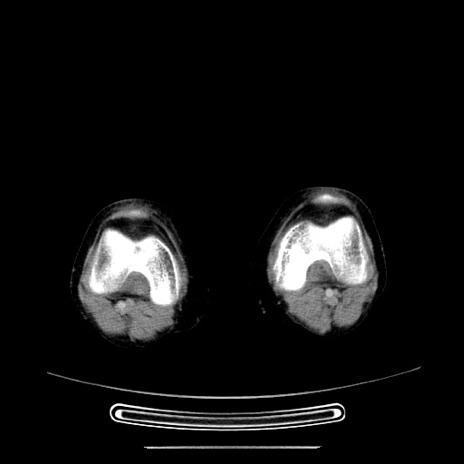

症例5(横断像)

【症例】70歳代女性

【主訴】お腹が張る

【現病歴】1週間くらい前から腹部膨満の自覚あり。昨日夜から増悪したため、本日救急外来受診。

【身体所見】意識清明、BT 36.5℃、BP 165/106mmHg、HR 80bpm、SpO2 98%、腹部:膨満、軟、自発痛・圧痛なし、触診にて不快感あり、腸蠕動音:減弱

【データ】WBC 12600、CRP 1.04